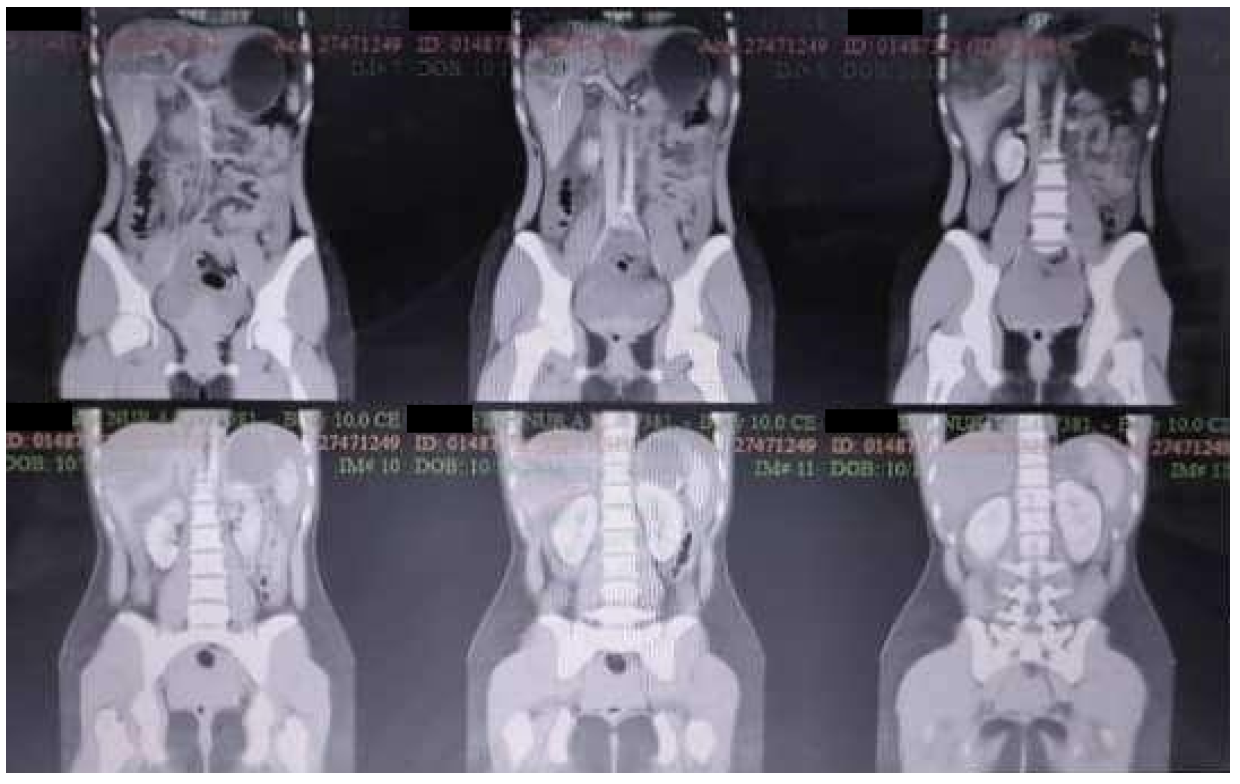

Then, the patient was sent to radiology for abdominal CT examination, with results showing spleen injury grade V (AAST rating scale) and free fluid in the abdominal cavity (Hematoperitoneum) (Figure 4).

Figure 4. Spleen Rupture Grade 5 (AAST Grading Scale), Free Fluid in the Abdominal Cavity (Hematoperitoneum)

In this case, the patient showed FAST (+) results in Morison Pouch, splenorenal, and perivesical. The FAST ultrasound results were then followed by a contrast CT scan of the abdomen and revealed a spleen rupture grade V and free intra-abdominal fluid. In this case, the results (+) in the Morison pouch and perivesical were not accompanied by rupture of the liver and rupture of the bladder.